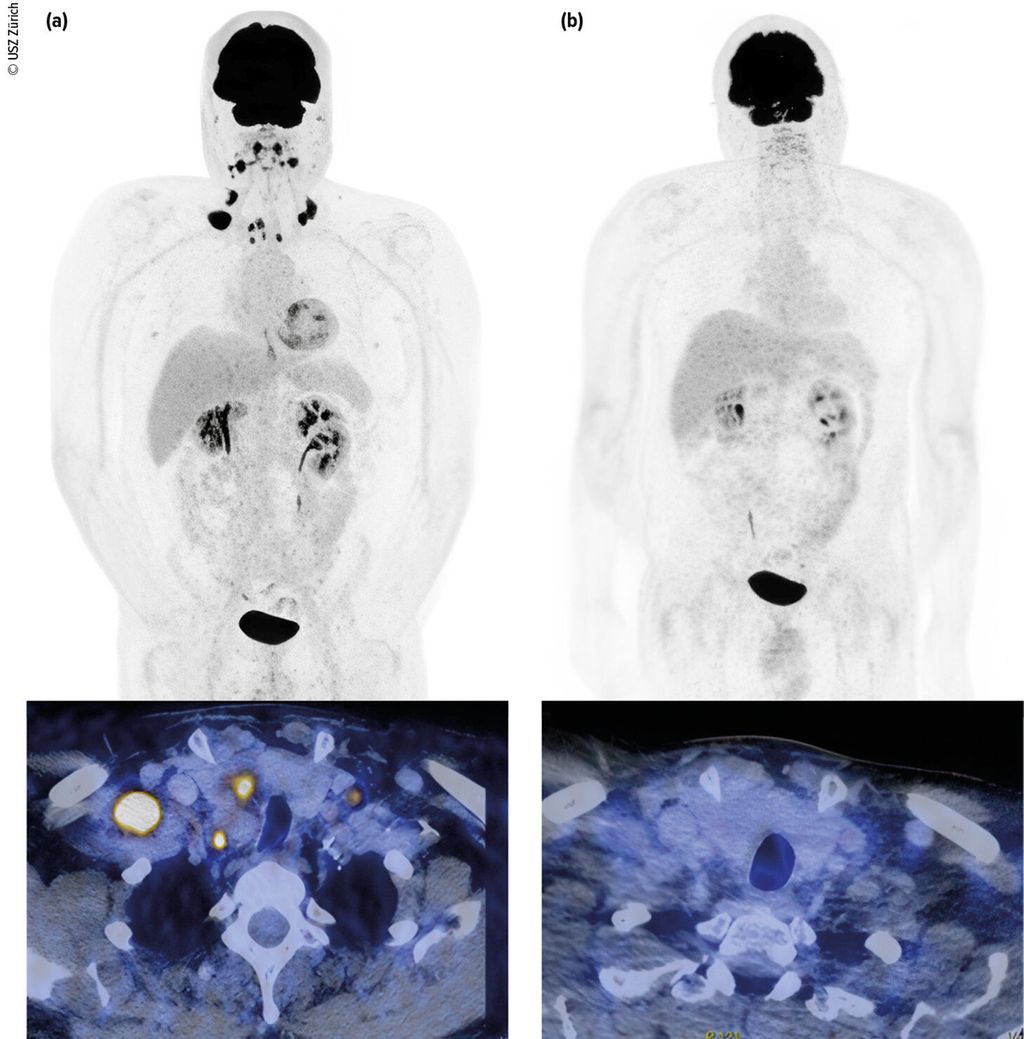

Fig.1: Carcinome urothélial de la vessie (initialement cT3 cN3 cM0) avec métastases lymphogènes métachrones. Classification par tomodensitométrie (TDM) avec diagnostic de métastases lymphogènes (a, à gauche). Première reclassification deux mois après le début du traitement par EV+P (b, à droite). L’image montre une rémission complète. Le patient est toujours en rémission durable. Images et patient de l’Hôpital universitaire de Zurich